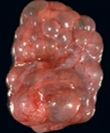

A kidney affected by Multicystic Dysplastic Kidney is ___ and made up of multiple ___ and little if any normal renal ___.

small, cysts, tissue

What is the most common source of palpable abdominal mass in infants?

Multicystic dysplastic kidney disease